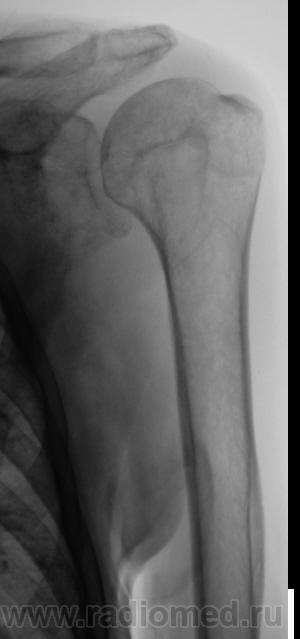

Пациент направлен хирургом на рентгенографию плечевого сустава. Травма, вроде-бы была. Хирург, не мудрствуя, направил пациента на рентгенографию. Пациент предъявляет жалобы на боли в области плечевого сустава, руку поднять не может. Врача-рентгенолога, на момент исследования в рентгеновском кабинете не было.

Валентин Львович, а с суставной впадиной лопатки все хорошо? У меня ее структура на подозрении...

Вы совершенно правы Татьяна Валентиновна. Я намеренно "обрезал" снимок, произведенный лаборантами, дабы акцентировать внимание на латеральном угле лопатки. Суставная поверхность лопатки и шейка внушают серьёзные подозрения, и с учетом "пороза" и структуры.

Но, я неоднократно повторяю, что работаю с очень хорошими лаборантами, и они прекрасно понимают, да и убедились, что если написано - рентгенография голеностопного сустава, то зачастую "написанное" не есть "то, что надо". Так и в данном случае лаборанты "захватили побольше", и дай бог, им здоровья и всего самого наилучшего.

Снимок "без обрезания" - ниже. Врача-рентгенолога в кабинете не было, лаборанты, оценив его, начали "пытать" пациента. Оказалось, что флюорографию органов грудной полости, этот пациент, "проходил" лет 5 тому. Ну, и лаборанты приступили к стандартному исследованию органов грудной полости.

При таких загонщиках этот махровый рак лёгкого – "лёгкая добыча рентгенолога". Со всей его свитой.